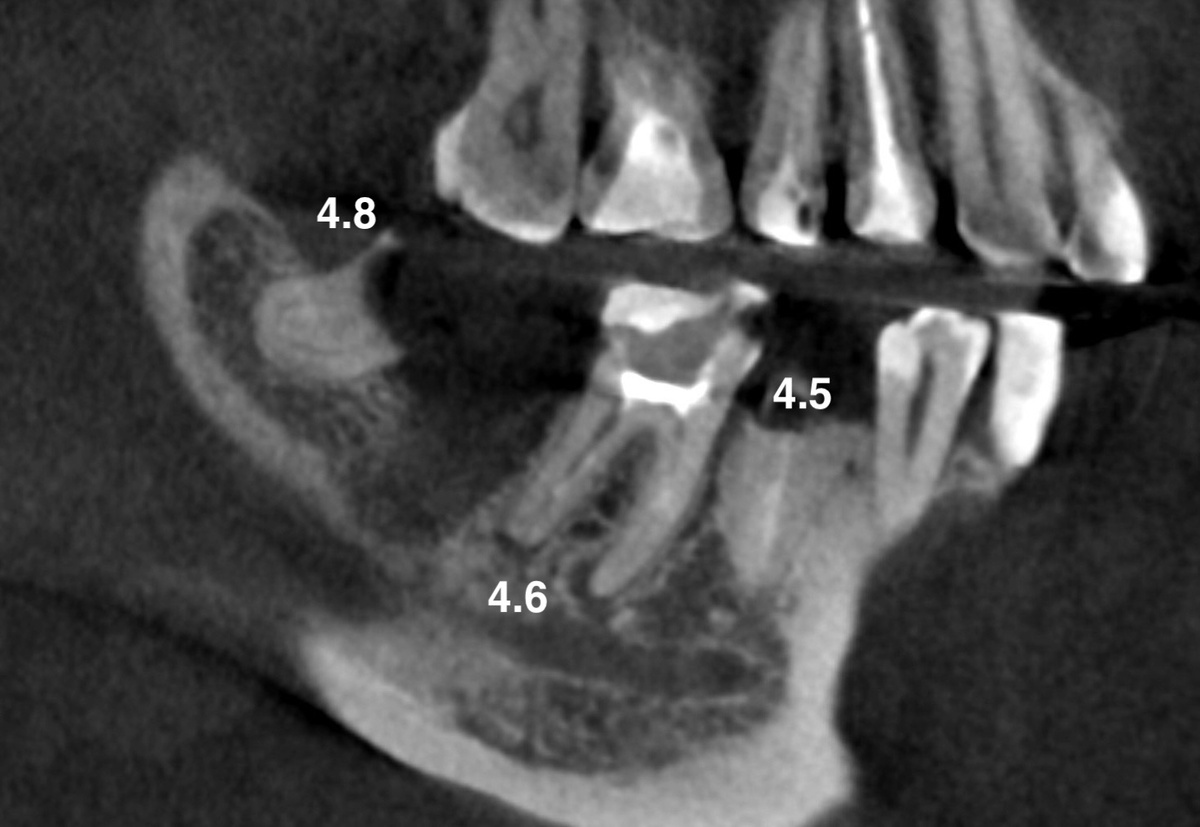

Давайте посмотрим на ситуацию в нижнем правом сегменте. 4.8 и 4.5 - под удаление:

КТ до лечения и удаления

4.7 уже удалили за месяц до приезда. И вот стоит одинокий, разрушенный 4.6 с периодонтитом, каналы его выглядят пустыми, коронковую часть "пожрал" кариес.

Стенки родные тонкие. Стенок мало. В каналах - цинкоксидэвгенольный цемент (кто знает - тот поймёт, удовольствие ещё то его оттуда доставать).